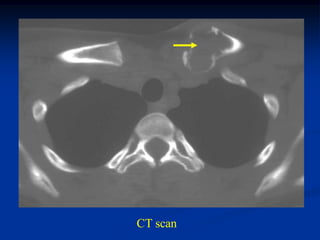

Case #989.7

5 year female with

UBC prox tibia

Lateral view

CT scan